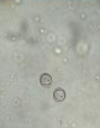

**Intestinal Coccidiosis 5-15 Days** (Especially 5-7 Days) * Isospora suis is most common. Also many Eimeria species can infect pigs. * Fetid, yellow to white diarrhea. Also can see “sheep pellet feces”. * Can be diagnosed by demonstration of **oocysts** in feces (see image) or demonstrating parasite in intestinal lesions. * Treated with **sulfamethazine or ponazuril**. * Prevention through fecal removal. Disinfection of farrowing facility is difficult due to hardy spores.